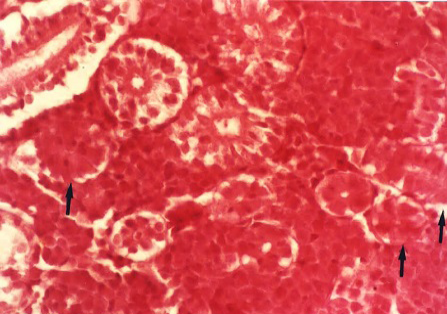

Figure 5

Oedema of the wall and hypertrophy of the endothelial cells in arterioles (arrows) and lymphoid depletion in the spleen (H&E x 400)